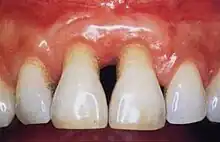

Gingivitis is a common condition that affects the gingiva or mucosal tissues that surround the teeth. The condition is a form of periodontal disease; however, it is the least devastating, in that it does not involve irreversible damage or changes to the periodontium (gingiva, periodontal ligament, cementum or alveolar bone). It is commonly detected by patients when gingival bleeding occurs spontaneously during brushing or eating. It is also characterized by generalized inflammation, swelling, and redness of the mucosal tissues. Gingivitis is typically painless and is most commonly a result of plaque biofilm accumulation, in association with reduced or poor oral hygiene. Other factors may increase a person's risk of gingivitis, including but not limited to systemic conditions such as uncontrolled diabetes mellitus and some medications. The signs and symptoms of gingivitis can be reversed through improved oral hygiene measures and increased plaque disruption. If left untreated, gingivitis has the potential to progress to periodontitis and other related diseases that are more detrimental to periodontal and general health.[10]

Healthy gingiva can be described as stippled, pale or coral pink in Caucasian people, with various degrees of pigmentation in other races. The gingival margin is located at the cemento-enamel junction without the presence of pathology. The gingival pocket between the tooth and the gingival should be no deeper than 1–3mm to be considered healthy. There is also the absence of bleeding on gentle probing.[11]